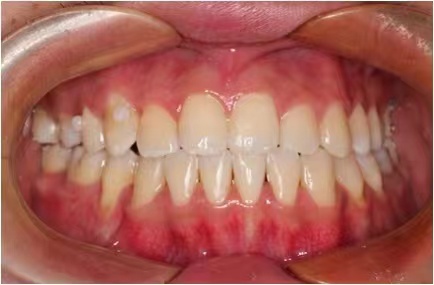

情况:不接受外科手术,在当地做了1年半的矫治,遇到困难无法进行。由外地正畸同行推荐来上海寻求非手术矫治的二手病例。武广增老师接收时的错合畸形情况,呈现严重的骨性反合偏合及侧方开合(图1-图10)。由于推荐其去口腔医院接受正颌外科手术遭到拒绝,武广增老师通过专业的检查、分析,制定一套详细的治疗计划,采用了磨牙推进器技术、武式辅弓技术等特色正畸手段获得明显效果(图2-1~图2-9)。治疗结束后也拍摄了相关照片(图3-1~图3-9)。

矫治后

图3-1